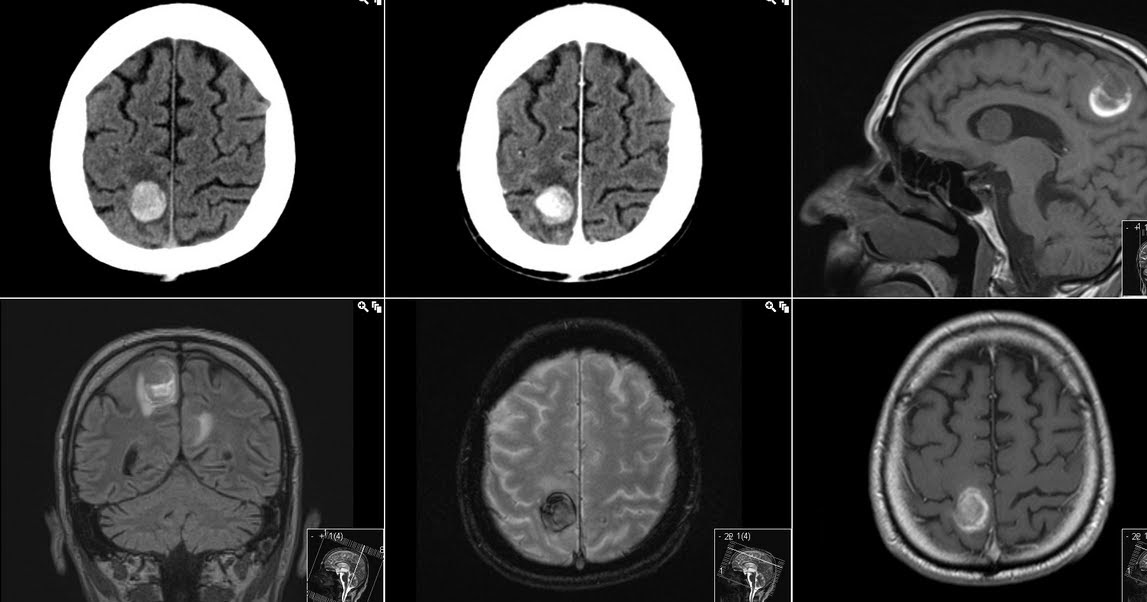

Diagnosis of Metastatic Brain Cancer

MRI Images of Brain Mets Signs Brain Mets changes in the senses: Common signs and symptoms of brain metastases include: the most common symptoms are: what are the symptoms of brain metastases? Weakness in the arms or legs. Brain metastases can impact your ability to hear, smell or see. Symptoms include pain, behavior changes, or seizures. Not being able to move parts of your body,. Signs Brain Mets.

Brain metastases Image Signs Brain Mets the most common symptoms are: Weakness in the arms or legs. what are the symptoms of brain metastases? This can include double vision or blurred. what are the symptoms of brain metastases? changes in the senses: A tumor makes pressure inside the skull, squeezing nearby brain tissue. brain metastases occur when cancer cells travel through. Signs Brain Mets.